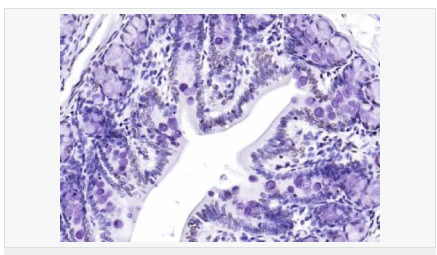

| 產(chǎn)品應用 | WB=1:500-2000 ELISA=1:5000-10000 IHC-P=1:100-500 IHC-F=1:100-500 Flow-Cyt=2ug/Test IF=1:100-500 (石蠟切片需做抗原修復) not yet tested in other applications. optimal dilutions/concentrations should be determined by the end user. |

| 免 疫 原 | KLH conjugated synthetic peptide derived from human CIDEC:101-200/238 |

| 產(chǎn)品介紹 | This gene encodes a member of the cell death-inducing DNA fragmentation factor-like effector family. Members of this family play important roles in apoptosis. The encoded protein promotes lipid droplet formation in adipocytes and may mediate adipocyte apoptosis. This gene is regulated by insulin and its expression is positively correlated with insulin sensitivity. Mutations in this gene may contribute to insulin resistant diabetes. A pseudogene of this gene is located on the short arm of chromosome 3. Alternatively spliced transcript variants that encode different isoforms have been observed for this gene. [provided by RefSeq, Dec 2010]. Tissue specificity: Expressed mainly in small intestine, heart, colon and stomach and, at lower levels, in brain, kidney and liver. Function: May act as a CEBPB coactivator in white adipose tissueto control the expression of a subset of CEBPB downstream targetgenes, including SOCS1, SOCS3, TGFB1, TGFBR1, ID2 and XDH (Bysimilarity). Binds to lipid droplets and regulates theirenlargement, thereby restricting lipolysis and favoring storage. Atfocal contact sites between lipid droplets, promotes directionalnet neutral lipid transfer from the smaller to larger lipiddroplets. The transfer direction may be driven by the internalpressure difference between the contacting lipid droplet pair. Whenoverexpressed in preadipocytes, induces apoptosis or increases cellsusceptibility to apoptosis induced by serum deprivation or TGFBtreatment. As mature adipocytes, that express high CIDEC levels,are quite resistant to apoptotic stimuli, the physiologicalsignificance of its role in apoptosis is unclear. Subunit: Interacts with CEBPB (By similarity). Interacts withCIDEA. Subcellular Location: Nucleus (By similarity). Endoplasmicreticulum (By similarity). Lipid droplet. Note=Diffuses quickly onlipid droplet surface, but becomes trapped and clustered at lipiddroplet contact sites, thereby enabling its rapid enrichment atlipid droplet contact sites. Tissue Specificity: Expressed mainly in adipose tissue, smallintestine, heart, colon and stomach and, at lower levels, in brain,kidney and liver. Post-translational modifications: Ubiquitinated and targeted to proteasomal degradation,resulting in a short half-life. Protein stability depends ontriaclyglycerol synthesis, fatty acid availability and lipiddroplet formation (By similarity). DISEASE: Note=In omental adipose tissue of obese patients matchedfor BMI, expression levels tend to correlate with insulinsensitivity. Expression is increased 2-3 fold in the group ofpatients with high insulin sensitivity, compared to theinsulin-resistant group. This observation is consistent with theidea that triglyceride storage in adipocytes plays an importantrole in sequestering triglycerides and fatty acids away from thecirculation and peripheral tissues, thus enhancing insulinsensitivity in liver and muscle. This effect is not significant insubcutaneous adipose tissue (PubMed:18509062). In subcutaneousadipose tissue of diabetic patients, tends to negatively correlatewith body mass index and total fat mass, independently of insulinsensitivity (PubMed:18334488). Similarity: Contains 1 CIDE-N domain. SWISS: Q96AQ7 Gene ID: 63924 Database links: Entrez Gene: 63924 Human Entrez Gene: 14311 Mouse Omim: 612120 Human SwissProt: Q96AQ7 Human SwissProt: P56198 Mouse Unigene: 567562 Human Unigene: 635072 Human Unigene: 10026 Mouse Unigene: 33794 Rat Important Note: This product as supplied is intended for research use only, not for use in human, therapeutic or diagnostic applications. |